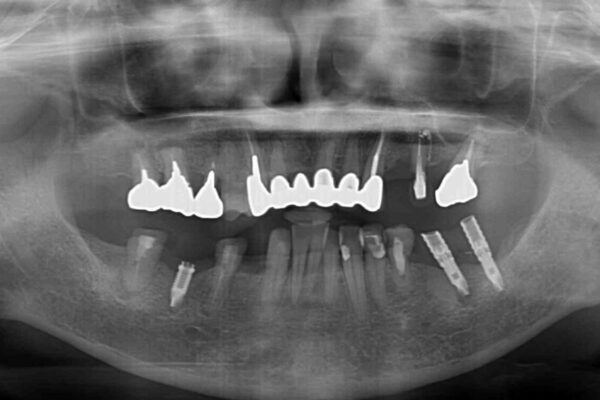

ご主人が当院に通院されていたことで、ご紹介により来院されました。 以前通院していた医院で、奥歯のインプラント埋入、前歯部のインビザライン矯正を行ったものの、そのまま放置してしまったとのことで来院された患者様です。

下顎前歯や上顎奥歯などをワイヤー装置により部分矯正を行い、歯列を整えた上でインプラント部分を含めてオールセラミッククラウンにて補綴治療を行うこととしました。

インプラント上の仮歯がボロボロになり、前歯に非常に負担のかかる状態であったため、早急に奥歯の仮歯を修復し、矯正治療、奥歯の補綴治療、前歯の補綴治療と順々に進めて行きました。